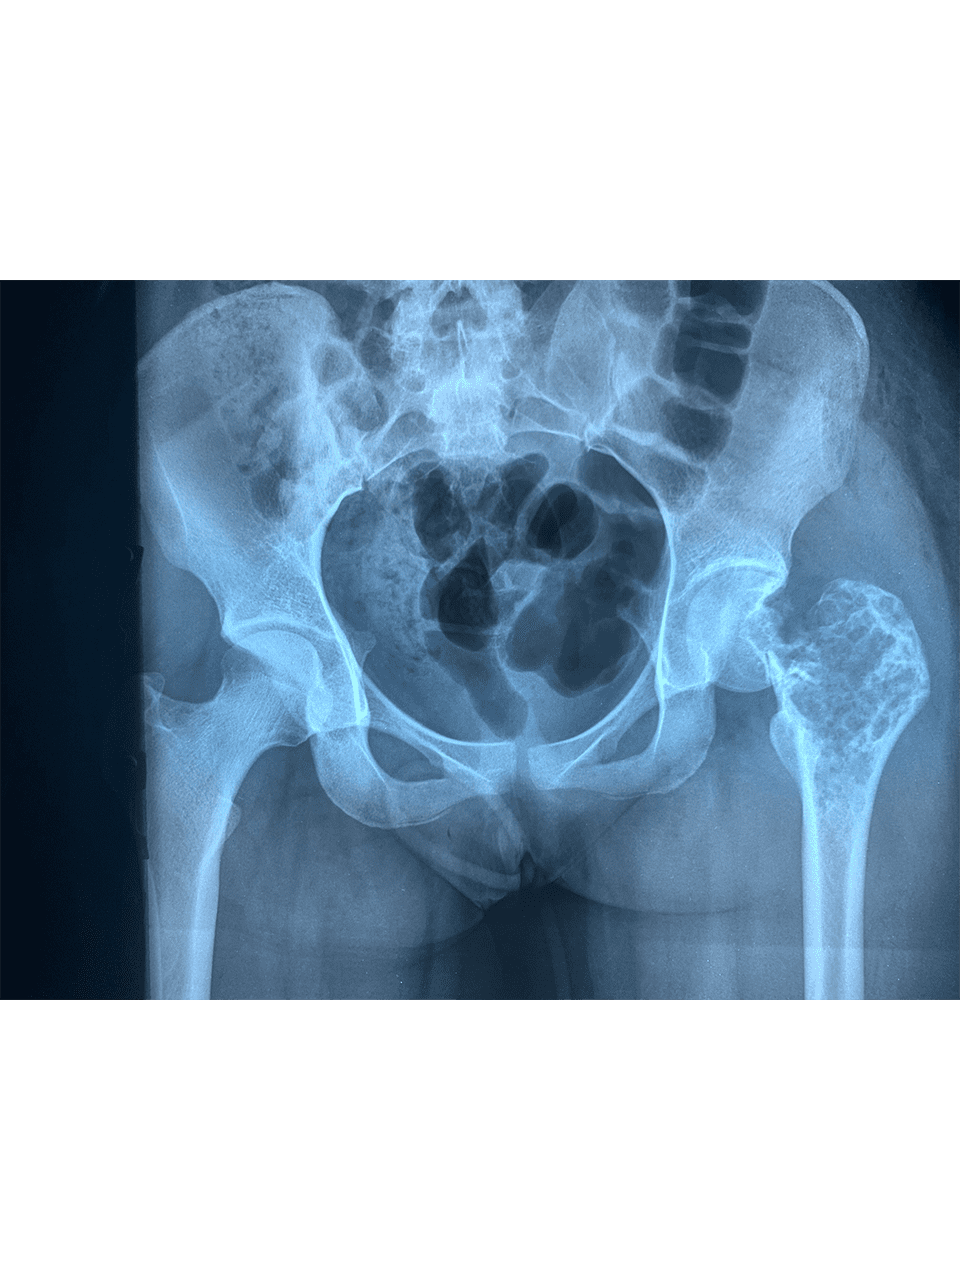

Dr. Weber and his partners participate in short term medical mission trips to Cambodia. Dr. Weber has had the pleasure of going twice now in 2018 and 2020. During these trips Dr. Weber performs total hip replacements on patients who normally would have no treatment options. To learn more and to see videos from the experience please click the links below.